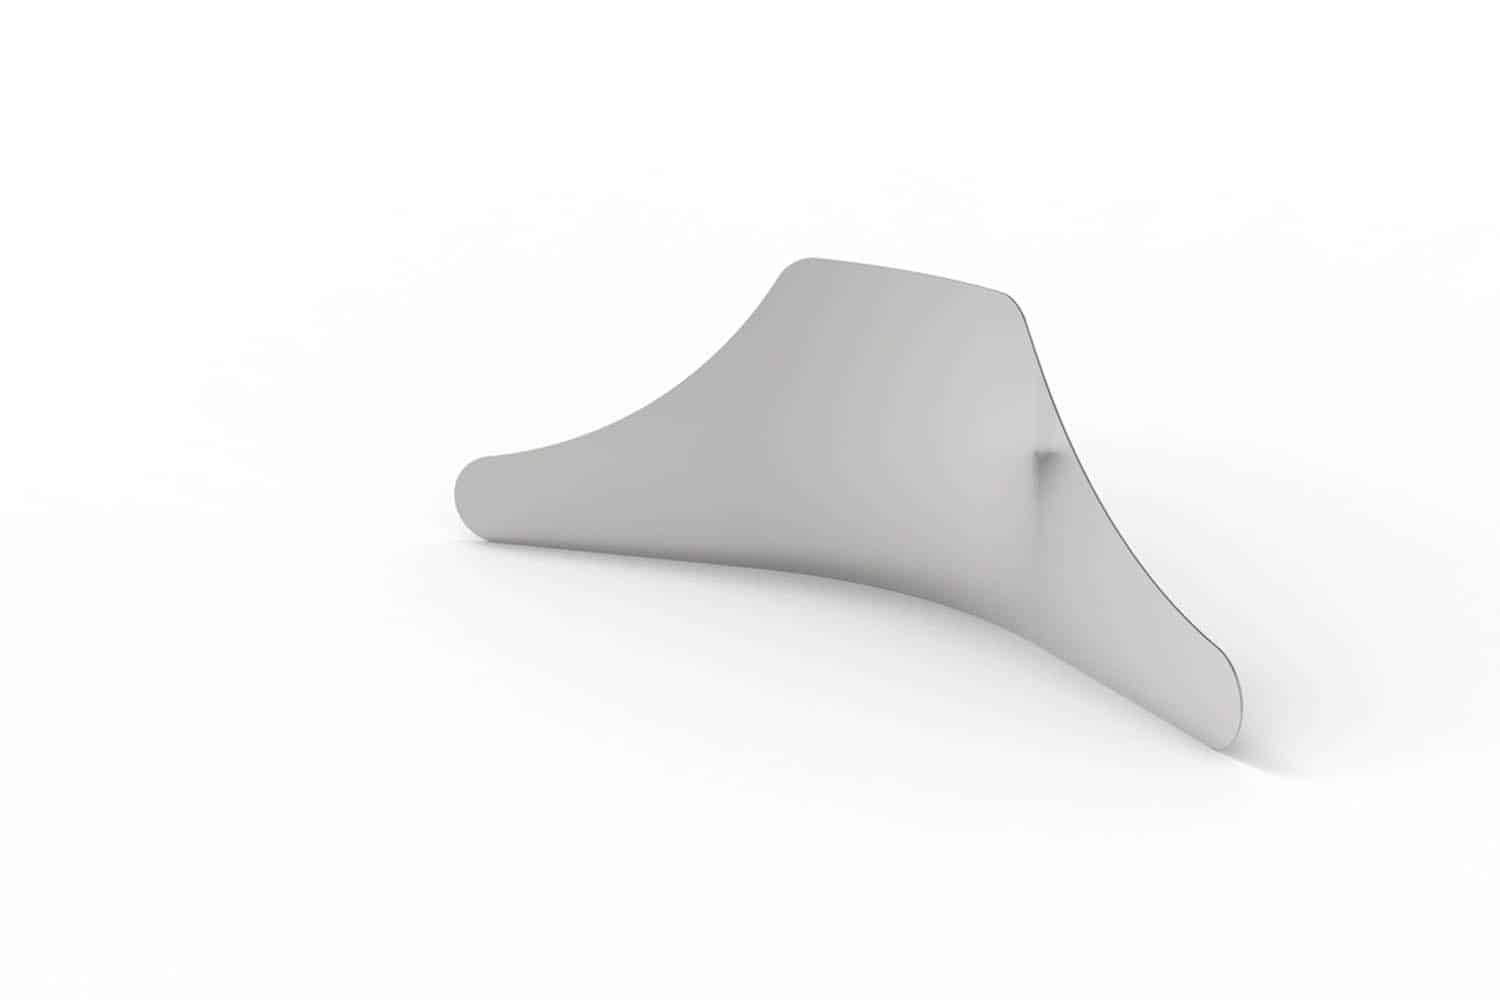

Excellent protection of adjacent teeth during preparation (sandblasting, etching, drilling)